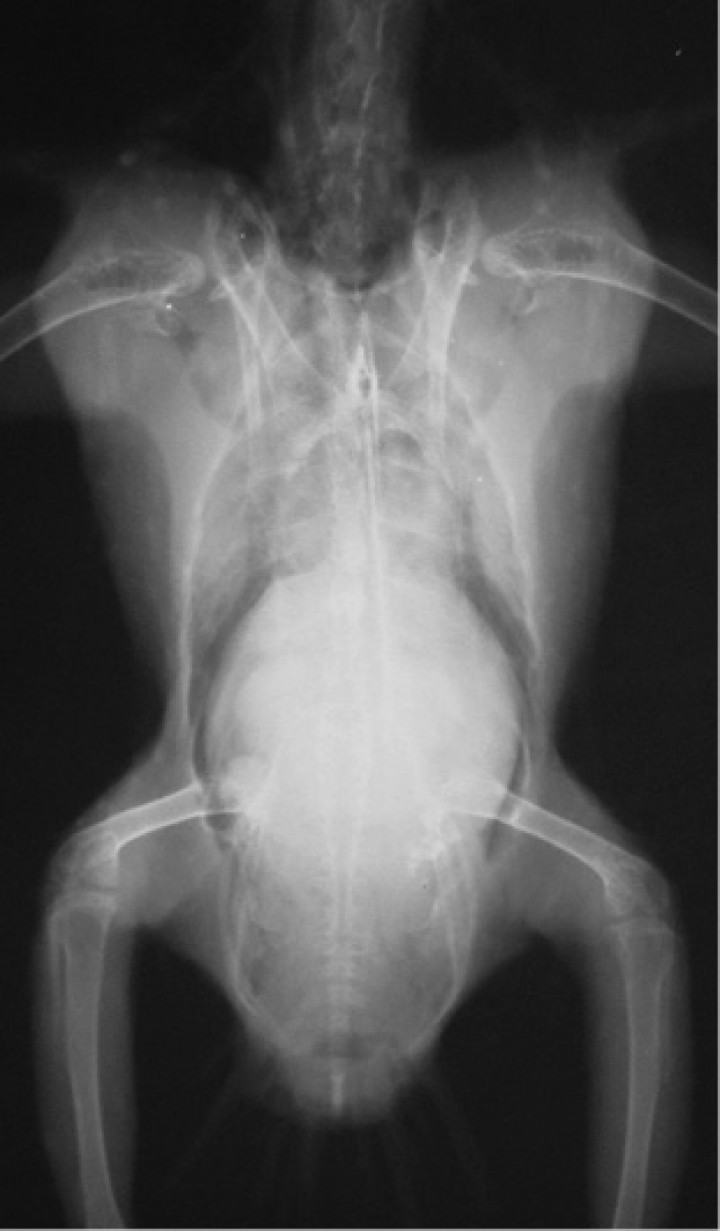

El estudio radiológico, realizado bajo anestesia general inhalatoria con isofluorano (IsoVet, Braun, Morpeth, Reino Unido) y oxígeno con mascarilla (inducción al 5% y mantenimiento al 3%), reveló un marcado aumento de la silueta hepática, además de un incremento de la radiodensidad en el campo pulmonar (Fig. 1).

<p>Proyección ventrodorsal de todo el cuerpo. Se observa hepatomegalia con silueta redondeada, así como un incremento difuso de la opacidad de ambos pulmones.</p>

Proyección ventrodorsal de todo el cuerpo. Se observa hepatomegalia con silueta redondeada, así como un incremento difuso de la opacidad de ambos pulmones.